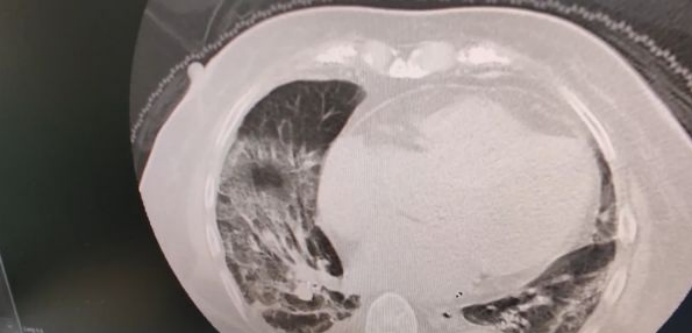

可四五天后,吴婆婆突然出现神志不清症状。家人还以为老人心脏病犯了,经送医检查,老人的血氧只有七十多,CT胸片情况更是惨不忍睹:双肺都已经白化!

武汉第四医院心内科主任成忠实介绍,正常人的CT,肺部都是黑色,可吴婆婆送来后双肺都已经白化,缺氧非常严重,几天高流量氧治疗效果都不好,一度要上呼吸机。像吴婆婆这样,没高烧,不咳嗽,但最终严重肺部感染而出现生命危险的情况,在医院里并不罕见。

众所周知,肺是呼吸器官,大量的气体交换需要在肺的肺泡中完成,正常情况下肺泡中只有空气,就像是干净的玻璃瓶;当奥密克戎病毒侵犯肺泡引起炎性反应时,大量的炎性渗出液渗出到肺泡中,“玻璃瓶子”便不再透明,肺泡被液体占据无法再完成气体交换,机体就会因缺氧而引发一系列问题甚至危及生命,后果还是较为严重的,通过肺部CT检查可以清楚地显示肺部呈白茫茫的一片。